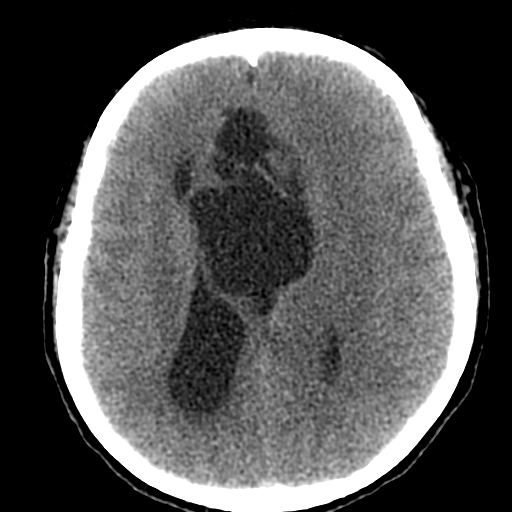

Мало что понимаю в КТ, но как то на ОНМК не тянет. Не могу понять почему сигнал (извините привыкла все сигналами оценивать) от образования какой же что и от желудочка?!

На объем как то тоже не похоже. , сигнал равномерный и такой же как и от ликвора. Если расценивать как последствия ОНМК так это как должно было " рвануть" да еще и с поражением желудочков - не пациент бы вряд ли выжел. Как же сложно в этом к/т ! Не знаю может это глупо, но у меня пока впечатление о врожденной патологии мозга. А с контрастом не делали ? Или вам и так все понятно, Сергей Николаевич , тогда поделитесь мыслями пожалуйста.

Создается впечатление о нехватке/недостатке мозгового вещества.

Действительно любопытно! Только сканов мало. Пока мысль о кисте полости межжелудочковой перегородки. Нет ли там где препятствия или изолированная киста?))

Эпидермоидная киста?

Я бы может сказала что здесь агенезия мозолистого тела. Как мне не хватает МРТ данных (. Агенезия ? Перегородки. Сергей Николаевич подскажите возраст пожалуйста. Здесь должна быть выраженная неврологическая клиника. Расскажите побольше о пациенте.

Эпидермоид может расти, при ТИА может быть случайной находкой. А тут ещё окклюзионная гидроцефалия.

Может, это две межполушарные арахноидальные кисты?

Сравните очертания кист в первом и последнем наблюдениях...

Больному около 55 лет, клинику дает не сколько само образование, а компрессия структур мозга, базально вообще беда (отчасти видно компреммию некоторых базальных цистерн мозга). Сразу скажу насчет эпидермоидной кисты - ДВИ не будет :)

Однозначно киста, значит, осталось выяснить какая, холестеатома или арахноидальная?